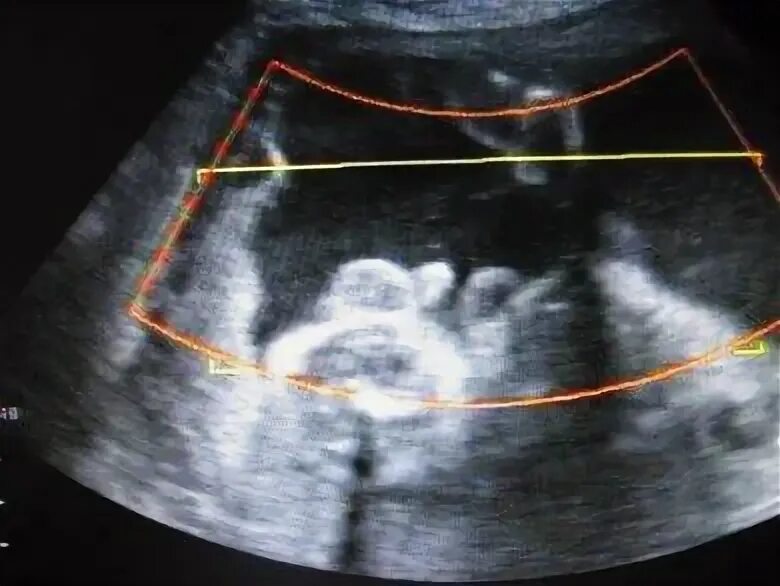

Может врач ошибиться с полом ребенка